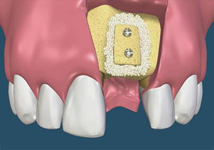

Sonic Weld Rx

Novinkou v augmentačních metodách, kterou jako první v České republice používáme v našem zařízení je ultrazvuková metoda pomocí polylaktidové membrány - SonicWeld Rx®, kterou zavedl do implantologie v roce 2009 Dr. Dr. G.Iglhaut (Memmingen, Německo).

Jedná se o augmentační metodu při dostavbách kosti a defektech kosti horní a dolní čelisti.

SonicWeld Rx